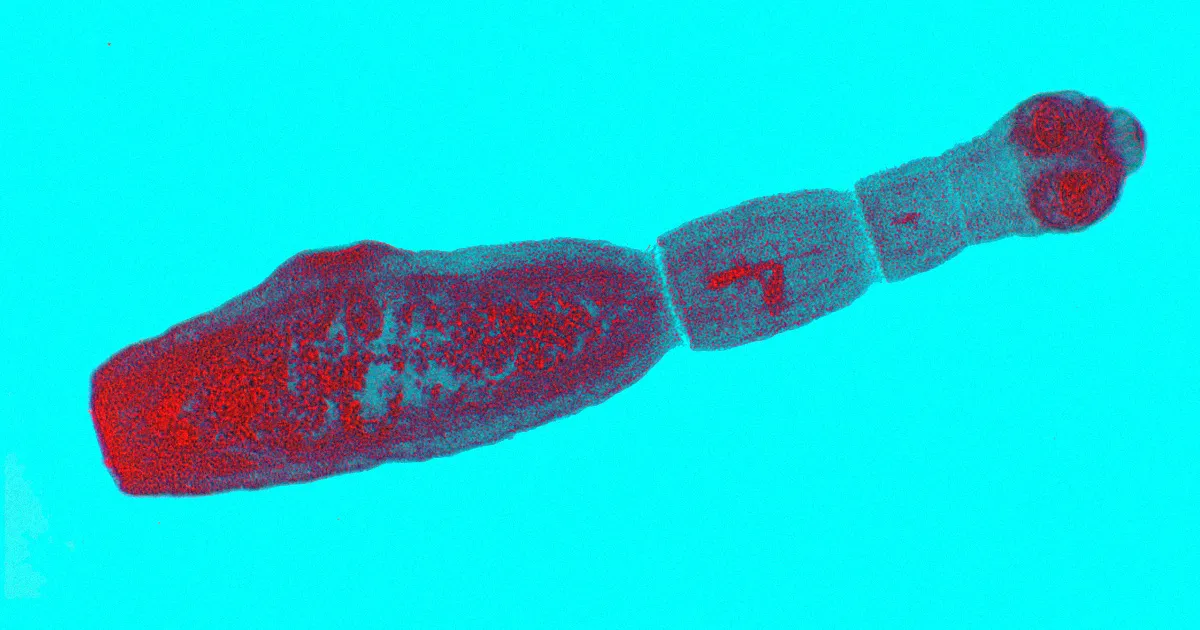

Des scientifiques mettent en garde : un parasite capable de passer des chiens aux humains a récemment été identifié au Canada. Ce phénomène inquiétant est attribué à une maladie parasitaire ressemblant au cancer, causée par des ténias. Des cas ont été rapportés dans la province canadienne de l’Alberta, selon des recherches récentes.

Houston a également rappelé que la pandémie de COVID-19 nous rappelle l’importance des maladies d’origine animale, incitant à rester vigilant face à de telles mutations. Selon lui, il existe un réel risque que cette vague d’infection se propage davantage. Les humains peuvent contracter cette maladie en ingérant des œufs microscopiques de Echinococcus multilocularis, souvent présents dans des aliments contaminés. Les symptômes peuvent imiter ceux du cancer du foie et mettent des années à se manifester. D’autres problèmes de santé associés incluent une fatigue, des douleurs abdominales et une perte de poids.

Cette maladie, connue sous le nom de echinococcosis alvéolaire (AE), peut s’avérer fatale si elle n’est pas traitée. Le traitement consiste souvent en l’ablation chirurgicale des tumeurs parasitaires. Il est crucial de noter que le long délai entre l’exposition et les symptômes – pouvant aller de 5 à 15 ans – rend cette maladie sournoise et difficile à détecter.

Une nouvelle étude révèle qu’un nouveau souche du parasite, plus virulente et capable de contagion, a trouvé un habitat au Canada. Entre 2013 et 2020, dix-sept cas de AE humaine ont été diagnostiqués, touchant des individus âgés de 19 à 78 ans, tous probablement affectés en Alberta.